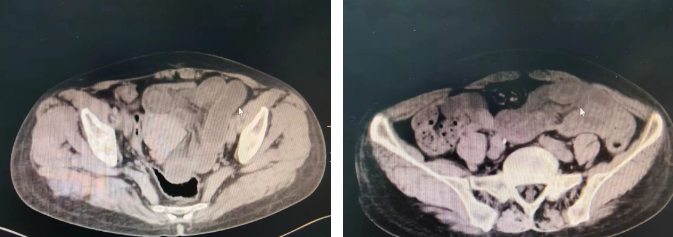

10小时前,裴先生无明显诱因再次出现上腹痛,呈持续性疼痛,弯腰屈膝位可缓解,伴恶心,频繁呕吐胃内容物,伴胸闷、憋气,血液淀粉酶AMY 111.00U/L;上腹部CT提示“急性胰腺炎”。

58岁的孙女士因突发下腹剧痛就诊,CT显示“肠扭转”。医生发现,她近1.2米的小肠已因缺血发黑坏死,立即启动绿色通道,从入院到完成腹腔镜手术仅用1小时,成功切除坏死肠管。